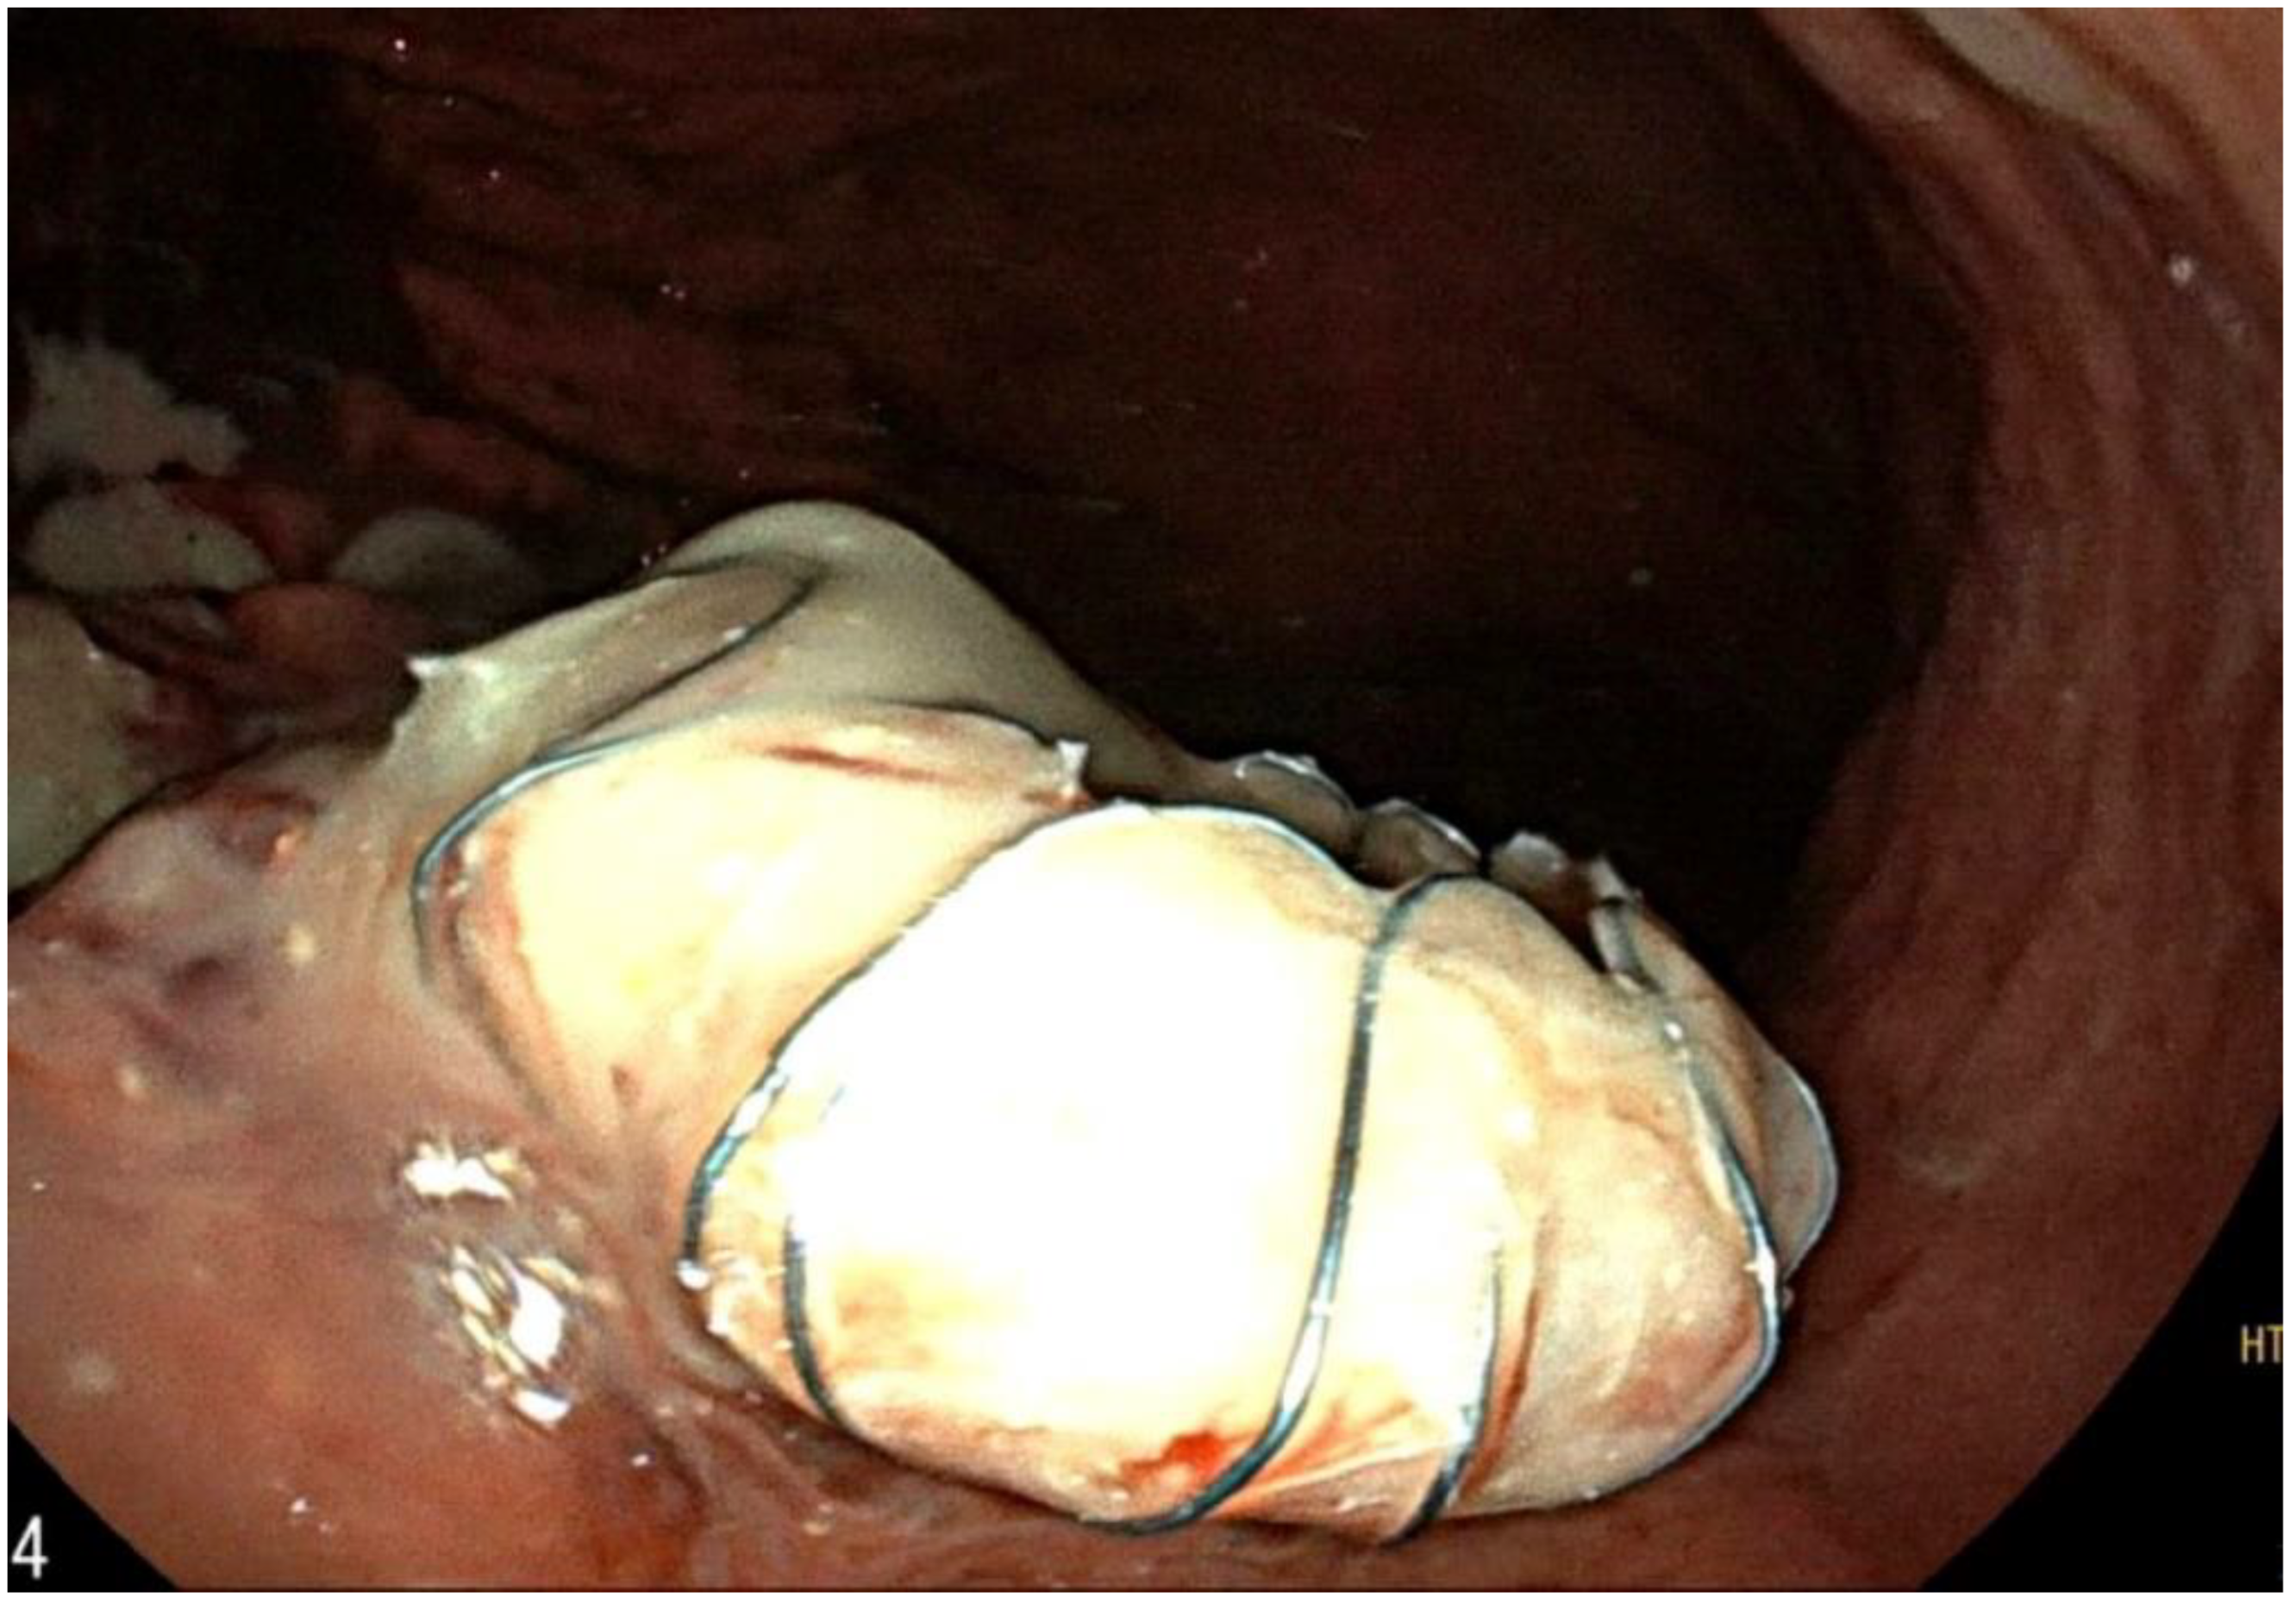

Successful Treatment of Pancreatic Pseudocysto-Duodenum Fistula with Ultrasound Endoscopic Drainage: A Case Report

2. Case Report